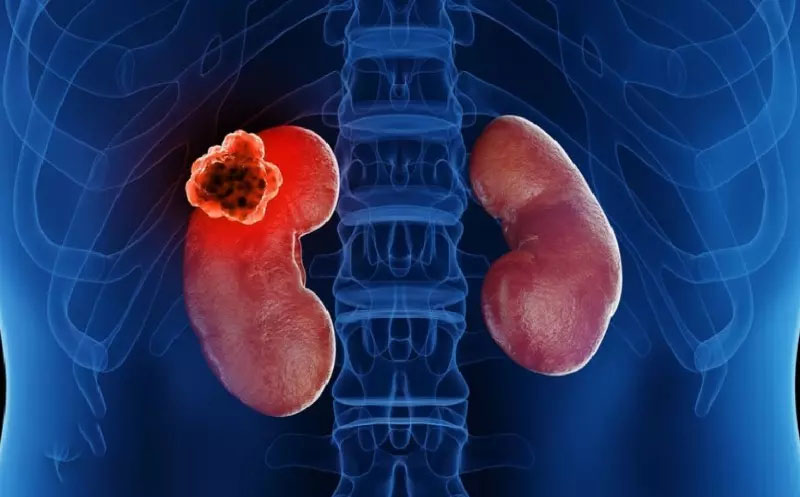

شناسایی تومورها و کیستها: اسکن کلیه برای شناسایی تومورها، کیستها یا سایر تودههای غیرعادی در کلیهها استفاده میشود. این تودهها ممکن است خوشخیم یا بدخیم باشند.

بررسی آسیبهای کلیوی پس از تصادف یا جراحی: پس از آسیب یا جراحی کلیه، اسکن میتواند برای بررسی میزان آسیب به کلیهها و عملکرد آنها مفید باشد.